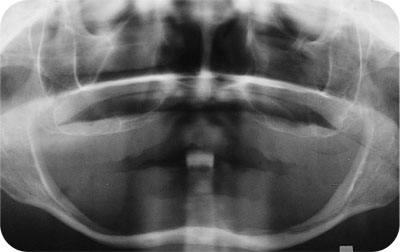

The anatomical changes which occur following extraction of natural teeth can broadly be divided into intraoral and extraoral changes. These will differ between individuals who remain partially dentate and those who are edentulous following tooth loss. As people age, loss of alveolar bone is inevitable. However, following total tooth loss, alveolar bone resorption is greatly increased. Alveolar bone height and width decrease markedly (Figs. 1-1 and 1-2). Most of this change occurs in the first year following extractions, but remains an inexorable process throughout life. Resorption occurs on the buccal aspect of the maxillary ridge and the lingual aspect of the mandibular ridge. In a mixed longitudinal study over 25 years, Tallgren demonstrated the extent of bone loss in edentulous individuals. She demonstrated that the loss of bone is four times greater in the mandible than the maxilla. Despite extensive research, the reason for great individual variation in bone loss remains unclear. It seems likely that a combination of local and systemic factors may be responsible for this phenomenon.

Fig 1-1 Orthopantomogram showing the edentulous jaws of a 62-year-old female. Note how thin the lower jaw is following extensive loss of alveolar bone.